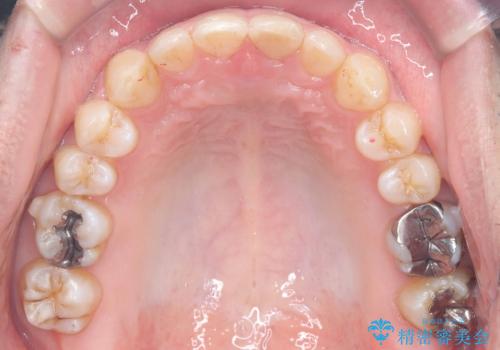

- 前歯の隙間と歯のデコボコを主訴にご来院された患者様です。

加えて、上下の奥歯が全く咬み合わないシザーズバイトの状態も認められました。

矯正検査の結果、非抜歯でインビザラインによる治療が可能と判断し、治療を行いました。